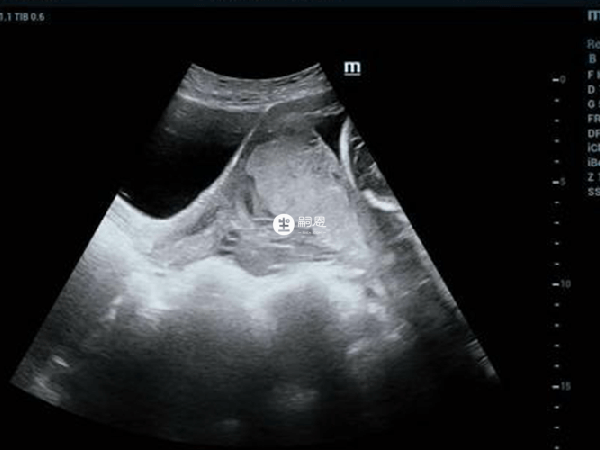

这个是通过B超检查直接测算出来的,不需要计算就可知道具体的值是多少,一般而言羊水深度的正常范围是3-7cm,超过或低于这个标准值就代表宝宝出现了异常情况,当数值差距过大时,可能会导致终止妊娠。

在临床上将羊水深度的测算称之为AFD测量法,也就是与孕妇最大羊水池与子宫轮廓相垂直的深度,所以羊水深度是测量单面子宫区域的羊水,除此之外目前比AFD算法更准确的是AFL计算法(也称羊水指数)。

羊水指的是怀孕女性子宫羊膜腔内的液体,测量方法有两种:一种是单个羊水池的垂直最大深度,另一种就是4个象限羊水最大垂直深度的总和,也称之为羊水指数,通过B超检测就可直接计算羊水深度,当单个羊水池不正常,那么就要再测量羊水指数。

在临床上,羊水指数是以脐水平线和腹白线为分割线,然后将子宫总共分为4个象限,然后再将这4个象限内羊水池的最大垂直直径相加,而羊水深度直接用B超测得,这两者都是用于判断女性的羊水量是多少,一般羊水深度的正常范围是3cm-8cm。